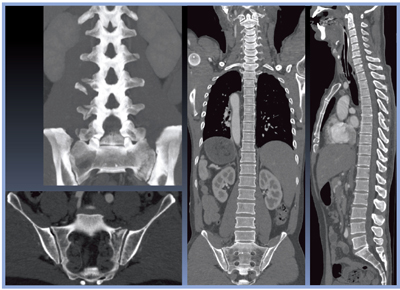

図3は,AIDR 3D Mildでの全身CT画像である。逐次近似応用再構成法を用いながらも,約1分で全身の再構成画像が得られることは,救急現場にとって大きなメリットである。

症例1の診断は,外傷性クモ膜下出血,右側頭葉脳挫傷,左耳介裂(左浅側頭動脈損傷),胸部大動脈損傷(峡部),仙骨骨折(L2〜L5の横突起骨折)であった。

図3 症例1:全身CT画像(AIDR 3D Mild)